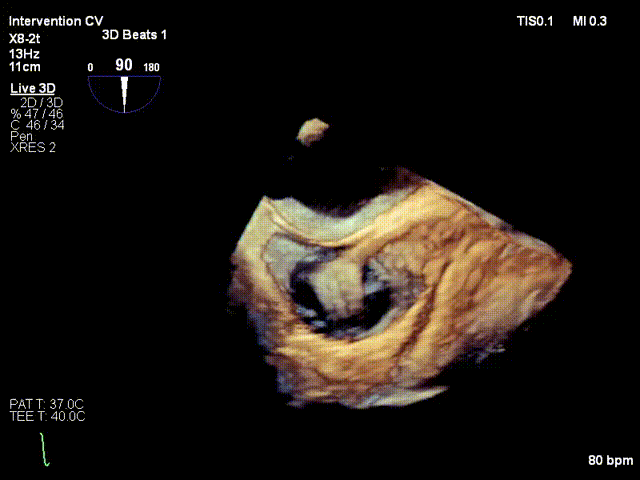

After the patient was placed under general anesthesia, the jugular vein was punctured intraoperatively to establish surgical access. An 18Fr delivery sheath was advanced along a stiff guidewire to the mid-inferior right atrium, and the delivery system was introduced under ultrasound guidance. A 12T K-Clip® device was implanted at the posterior annulus, and another 12T K-Clip® device at the anteroposterior annulus respectively. The angle between the device and the annulus plane was adjusted through catheter deflection and rotation, directing the tip of the clip device to the target position. The anchoring component was deployed into the annulus under ultrasound MPR mode; after confirming stable traction, the clamping arms were opened and apposed to the annulus, followed by retraction of the anchoring component to close the clamping arms for annuloplasty. The surgical effect was evaluated as satisfactory, and the clip components were then released.

Opening the clamping arms, adjusting the direction and apposing to the annulus

Releasing the clip after closure